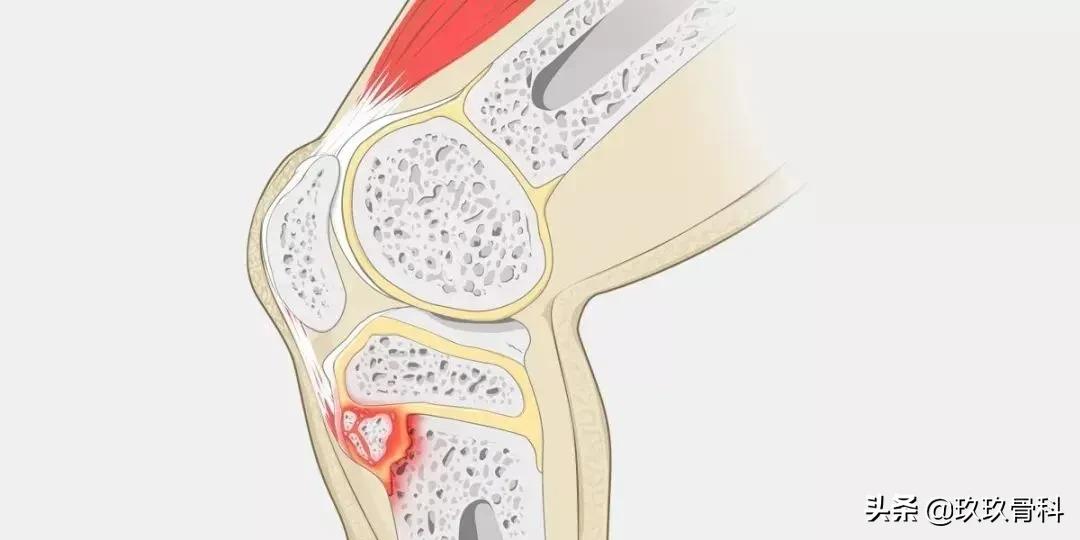

胫骨结节骨骺未融合,衔接薄弱,容易受到损伤。当进行跑、跳、踢等剧烈运动时,股四头肌长期、猛烈收缩,可使髌韧带反复牵拉附着处的胫骨结节,致结节软骨慢性损伤,引起创伤性炎症和修复性反应,造成胫骨结节炎和局部隆起。

1.早期表现为局部软组织肿胀,髌韧带增粗肥厚显著,继之则产生肌腱的钙化和骨化,胫骨结节呈舌状隆突,密度增高、碎裂,且与骨干轻度分离,形成大小、形态不一的骨碎块。